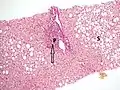

Pathology

Macroscopically, the liver is initially enlarged, but with the progression of the disease, it becomes smaller. Its surface is irregular, the consistency is firm, and the color is often yellow (if associated with steatosis). Depending on the size of the nodules, there are three macroscopic types: micronodular, macronodular, and mixed cirrhosis. In the micronodular form (Laennec's cirrhosis or portal cirrhosis), regenerating nodules are under 3 mm. In macronodular cirrhosis (post-necrotic cirrhosis), the nodules are larger than 3 mm. Mixed cirrhosis consists of nodules of different sizes.[37]

Micronodular cirrhosis, with diffuse areas of pallor.

However, cirrhosis is defined by its pathological features on microscopy: (1) the presence of regenerating nodules of hepatocytes and (2) the presence of fibrosis, or the deposition of connective tissue between these nodules. The pattern of fibrosis seen can depend on the underlying insult that led to cirrhosis. Fibrosis can also proliferate even if the underlying process that caused it has resolved or ceased. The fibrosis in cirrhosis can lead to destruction of other normal tissues in the liver: including the sinusoids, the space of Disse, and other vascular structures, which leads to altered resistance to blood flow in the liver, and portal hypertension.[38]